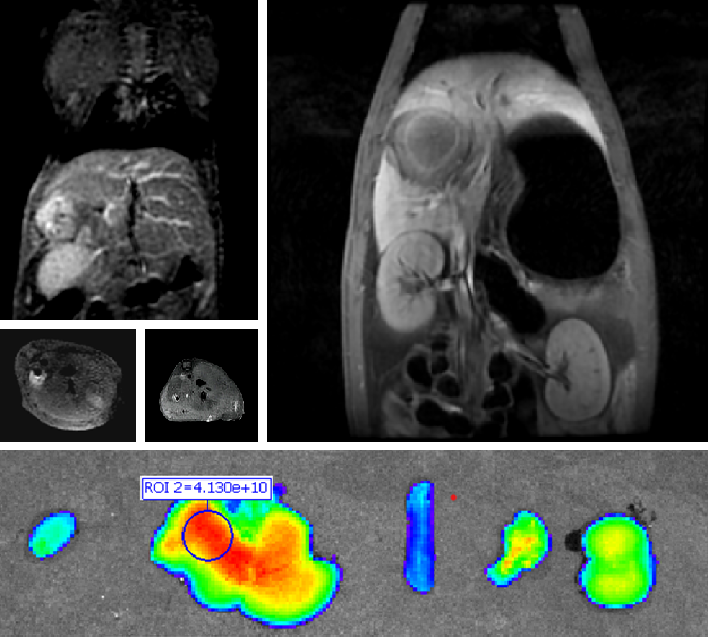

PL002是浙江普利药业有限公司研发的荧光/磁共振双模态造影剂,开发荧光/磁共振双模态造影剂成为提高原发性肝癌手术效率的有效方案。双模态造影剂的荧光成像能力可用于肝癌术中荧光导航,而磁共振增强能力可用于在术前判断肝脏代谢能力,推测肿瘤及肝脏对造影剂的摄取情况,提高肿瘤诊断精度,降低术前规划难度。

PL002相较于吲哚菁绿具有明显优势。目前吲哚菁绿在临床使用中存在给药到手术时间不确定的问题,可能造成病灶与正常组织对比度不足,影响术中的病灶的判断,PL002采用独特的钆络合物与荧光分子共价键结合的分子结构设计,这种设计能够让医生在术前通过磁共振成像确定造影剂在病灶中的聚集情况,进而针对患者个体情况来对手术时间进行规划。同时,由于PL002体内更为稳定,在荷瘤小鼠模型中同等条件下荧光成像效果维持时间长于现有荧光造影剂,也保证了其在临床应用中具有更宽的手术窗口。